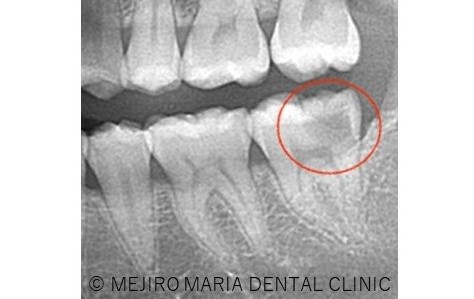

夜になるとズキズキ痛みがでることを主訴に来院された患者様です。1年前に他の歯科医院を受診したのを最後にクリーニングや定期検診には通っておられませんでした。

診査の結果、虫歯の進行はレントゲン上歯髄まで達していると思われましたが、厳密な歯髄診査の結果、診断は可逆性歯髄炎であり、生活歯髄保存療法が適応になると判断いたしました。